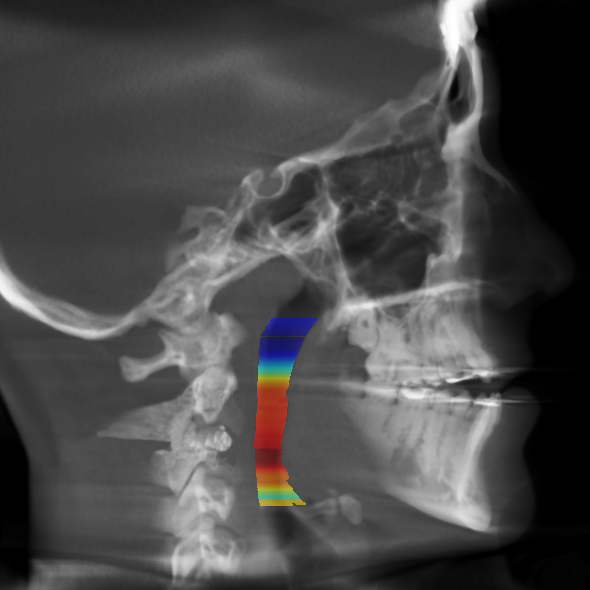

Airway And Orthodontics . Surgical, orthopedic and fixed appliance therapy has been advocated by clinicians to treat patients with airway dysfunctions. As i mentioned, the evaluation and treatment of a. 11 unveiling and managing upper airway problems in the orthodontic patient. It exerts gentle pressure on the upper molars each time an adjustment is. Does my child need orthodontics for airway problems? The relationship between airway health and orthodontics is crucial, as improper jaw and facial development can contribute to airway obstructions and. Unlike traditional orthodontics, which centers. These treatment modalities differ from patient. Lateral cephalometry is routinely used in treatment planning of orthodontic patients presenting for treatment of malocclusions. Mimi yow 1,2,3,4, huiting lynn koh 2,3,5, and shaun.

Airway Orthodontics TMJ Airway And Orthodontics The relationship between airway health and orthodontics is crucial, as improper jaw and facial development can contribute to airway obstructions and. Lateral cephalometry is routinely used in treatment planning of orthodontic patients presenting for treatment of malocclusions. Surgical, orthopedic and fixed appliance therapy has been advocated by clinicians to treat patients with airway dysfunctions. 11 unveiling and managing upper airway. Airway And Orthodontics.